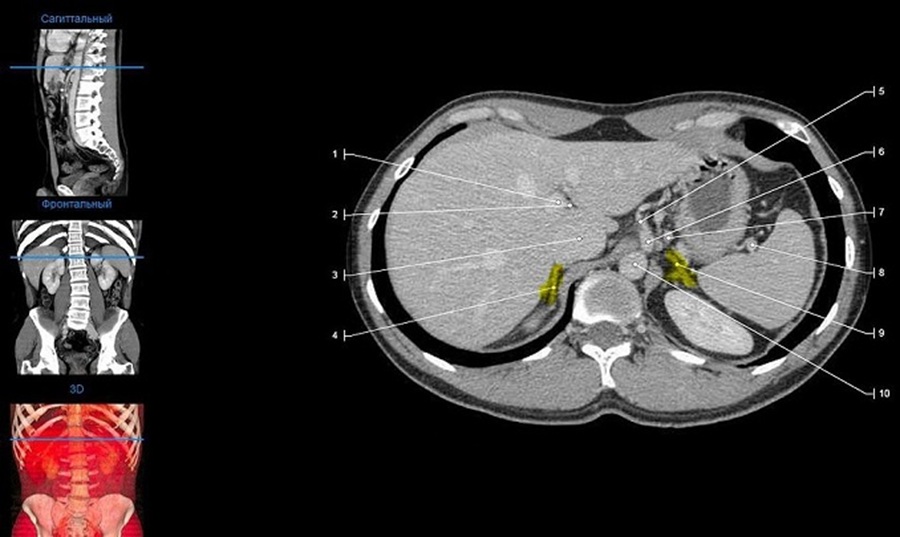

Процедура компьютерной томографии надпочечников представляет собой безопасное, относительно быстрое и технически чётко выстроенное обследование. Перед началом пациент проходит регистрацию и краткое медицинское интервью с сотрудником клиники. После этого его приглашают в томографический кабинет, где предлагают снять металлические предметы и лечь на выдвижной стол аппарата. Положение пациента фиксируется для исключения лишних движений, так как даже незначительное смещение может повлиять на качество снимков.

Сканирование проводится в положении лёжа, обычно на спине. Стол медленно задвигается в кольцо томографа, внутри которого расположены рентгеновские датчики. Аппарат начинает вращаться, создавая послойные изображения исследуемой области. Во время процедуры важно сохранять полную неподвижность, а по команде медицинского персонала – задерживать дыхание на несколько секунд. Это необходимо для устранения артефактов, вызванных движением диафрагмы. Весь процесс занимает от 5 до 15 минут в зависимости от сложности исследования.

Если используется контрастное усиление, перед сканированием внутривенно вводят препарат на основе йода. В момент введения пациент может почувствовать лёгкое тепло или привкус металла во рту – это нормальная реакция. После завершения обследования пациенту рекомендуется в течение дня пить больше жидкости, чтобы ускорить выведение контраста из организма. Результаты исследования, как правило, доступны через 1-2 дня, а в некоторых клиниках – уже через несколько часов. Врач-рентгенолог подготавливает заключение, описывающее выявленные изменения, и, при необходимости, рекомендует дальнейшие шаги для диагностики или лечения.

Компьютерная томография надпочечников обеспечивает детальное изображение этих желез и прилегающих структур, что особенно ценно при подозрении на малозаметные или сложные для диагностики нарушения. В отличие от ультразвукового исследования, КТ позволяет рассматривать надпочечники в объёмной проекции с высокой чёткостью. Снимки позволяют врачу оценить форму, размеры, симметрию, плотность тканей и выявить даже небольшие патологические изменения. Благодаря послойному сканированию можно зафиксировать мельчайшие отклонения, что существенно повышает точность диагностики и помогает выявлять проблемы на самых ранних этапах.

Среди наиболее частых находок – доброкачественные новообразования, такие как аденомы, которые отличаются от окружающей ткани по плотности и структуре. Также КТ может выявить феохромоцитомы, злокачественные опухоли, метастатические поражения, кисты или гиперплазию. Важную диагностическую роль играют данные о гомогенности ткани, наличии кальцинатов, некротических участков и особенностях сосудистого рисунка. При подозрении на воспалительные или дегенеративные изменения, КТ позволяет оценить степень вовлечения соседних структур – почек, сосудов, лимфоузлов.